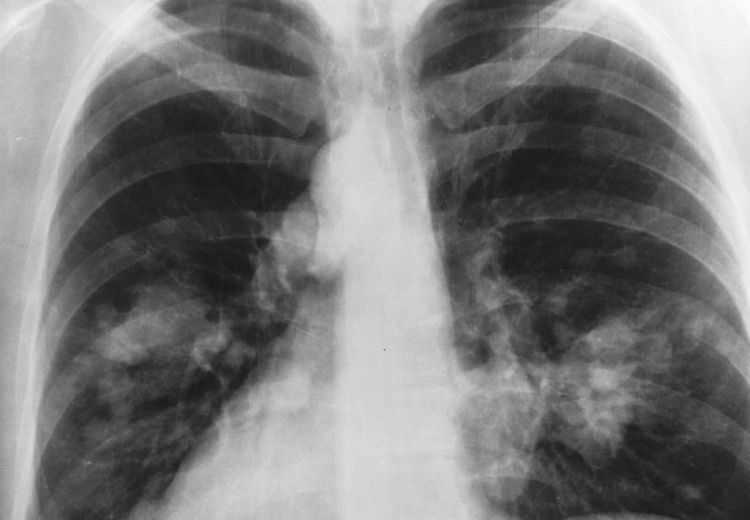

Thomas' experiences were detailed in an article by UW Health. “She had multiple lesions in her brain and disease on both lungs, and she was delirious for sure,” said her oncologist Anne Traynor, MD (pictured), associate professor (CHS), Hematology, Medical Oncology and Palliative Care.

Image (top): An example of an X-ray of the chest, courtesy of National Institutes of Health-National Cancer Institute. (public domain)